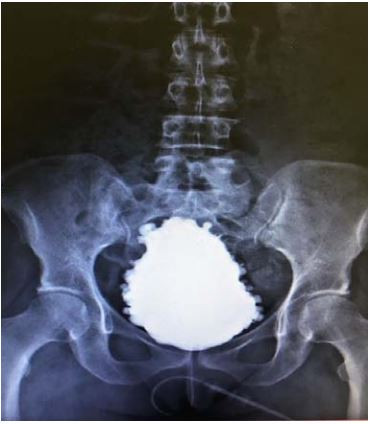

Mulher, 30 anos, história de infecção urinária de repetição desde a infância, tratada com vários ciclos de antibiótico. Exames laboratoriais: creatinina 0,9 mg/dL; exame de urina: hemácias 4/campo, leucócitos 12/campo, proteína ausente. Urocultura negativa. Investigação metabólica para litíase negativa. Medicação atual: hidroclorotiazida 12,5 mg, amitriptilina 25 mg, nitrofurantoína 100 mg e contraceptivo oral. Ultrassonografia abdominal: rins tópicos, dimensões normais. Urodinâmica: hiperatividade de detrusor

Uretrocistografia (fase miccional):

A conduta é: